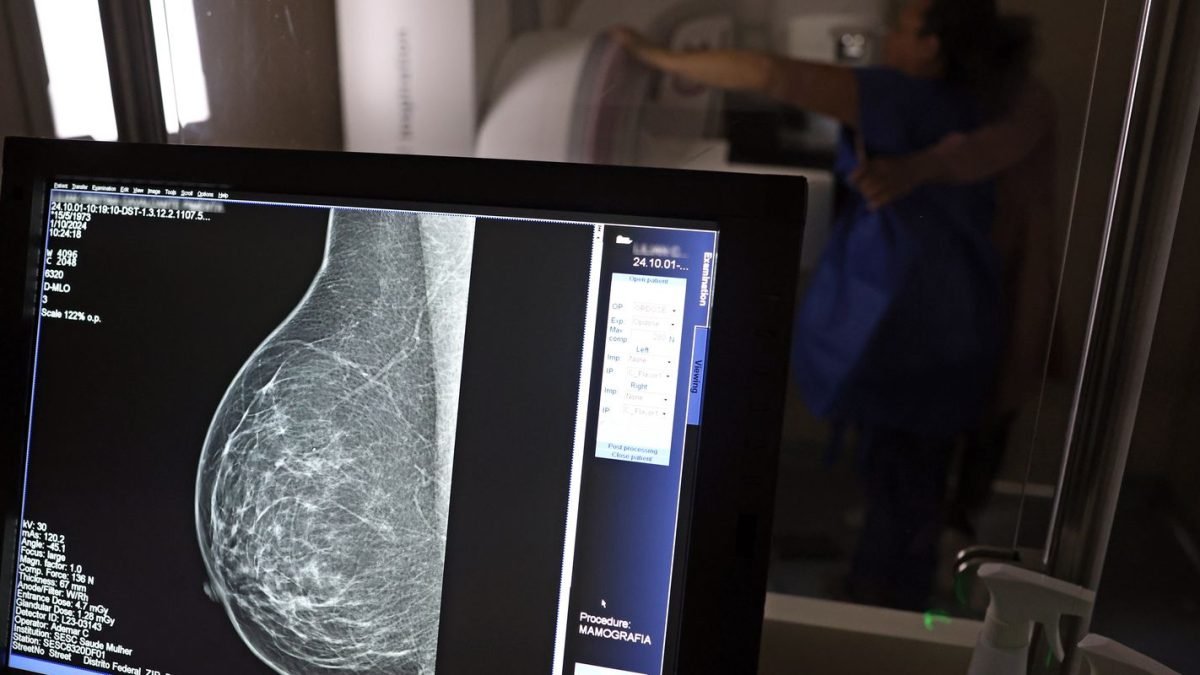

A Advocacia-Geral da República (AGU) informou nesta quinta-feira (20) ter aberto uma ação civil pública contra o médico Lucas Ferreira Mattos, por ele ter dito em postagem nas redes sociais que o exame de mamografia causa câncer de mama.

“Vamos acompanhar? Acompanhar o quê, se o médico não está fazendo nada para resolver. Ficar fazendo mamografia? Uma mamografia gera uma radiação para a mama equivalente a 200 raio-x. Se aumenta a incidência de câncer de mama por excesso de mamografia. Eu tenho 100% de certeza que seu nódulo benigno é deficiência de iodo”, disse o médico na ocasião, em uma resposta em vídeo.

O caso levou os conselhos regionais de medicina de Minas Gerais e São Paulo a abrirem investigações tendo o médico como alvo. O Instituto Nacional do Câncer (Inca) também informou, à época, não haver evidência de que a mamografia possa causar câncer de mama e que, pelo contrário, o exame previne a doença.

O órgão anexou ao processo nota técnica do Ministério da Saúde segundo a qual “é recomendado que mulheres de 50 a 69 anos, de risco padrão, façam uma mamografia de rastreamento a cada dois anos. Esse exame pode ajudar a identificar o câncer antes de a pessoa ter sintomas”.